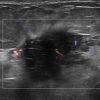

Ung thư vú

Ung thư vú - Ảnh 5

» Thông tin: Nữ giới – 58 tuổi.

» Lâm sàng: Khối tuyến vú.